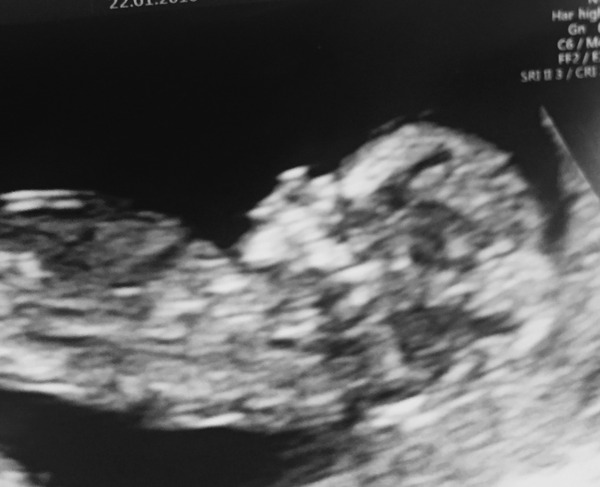

bearhuggy · 27/01/2016 17:06

lovely scan clara !!!

Was just looking through my scan pics again this morning and noticed this one which I had originally missed...baby is casually sitting there with its hands behind its head! what a little chiller.

August 2016 (3) - scans fast approaching, teeny tiny bumps appearing, and sickness easing....we hope!

bear, what a brilliant little one, just hanging out in there...! fingers crossed he/ she will be that chilled after arriving here!